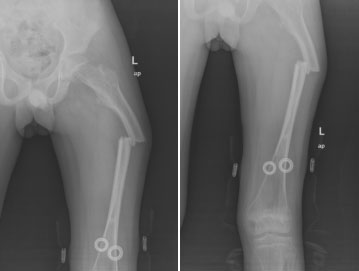

上圖為患者右側(cè)股骨干弓形變影像學(xué)資料

患兒入院后,小兒骨科針對(duì)患者病情及時(shí)召開病歷討論專題會(huì),經(jīng)分析,患兒為成骨不全患者,骨質(zhì)脆弱易骨折,由于缺乏活動(dòng)及生物力學(xué)刺激,加重骨丟失,陷入了“骨折制動(dòng)-快速骨量丟失-再骨折”的惡性循環(huán)。結(jié)合該患者相關(guān)病史、查體及輔助檢查患者診斷為:1.成骨不全癥;2.左股骨干骨折;3.股骨弓形變??紤]左股骨干中上段骨折,骨折端明顯移錯(cuò)位、成角、短縮及旋轉(zhuǎn),符合骨折切開復(fù)位內(nèi)固定術(shù)手術(shù)指征,但成骨不全癥患兒用鋼板固定后由于鋼板的應(yīng)力作用,往往更加容易出現(xiàn)內(nèi)固定失效,內(nèi)固定周圍發(fā)生醫(yī)源性應(yīng)力骨折,彈性髓內(nèi)釘由于缺乏強(qiáng)力的支撐,后期容易出現(xiàn)骨折不愈合,內(nèi)固定失效,弓形變等。